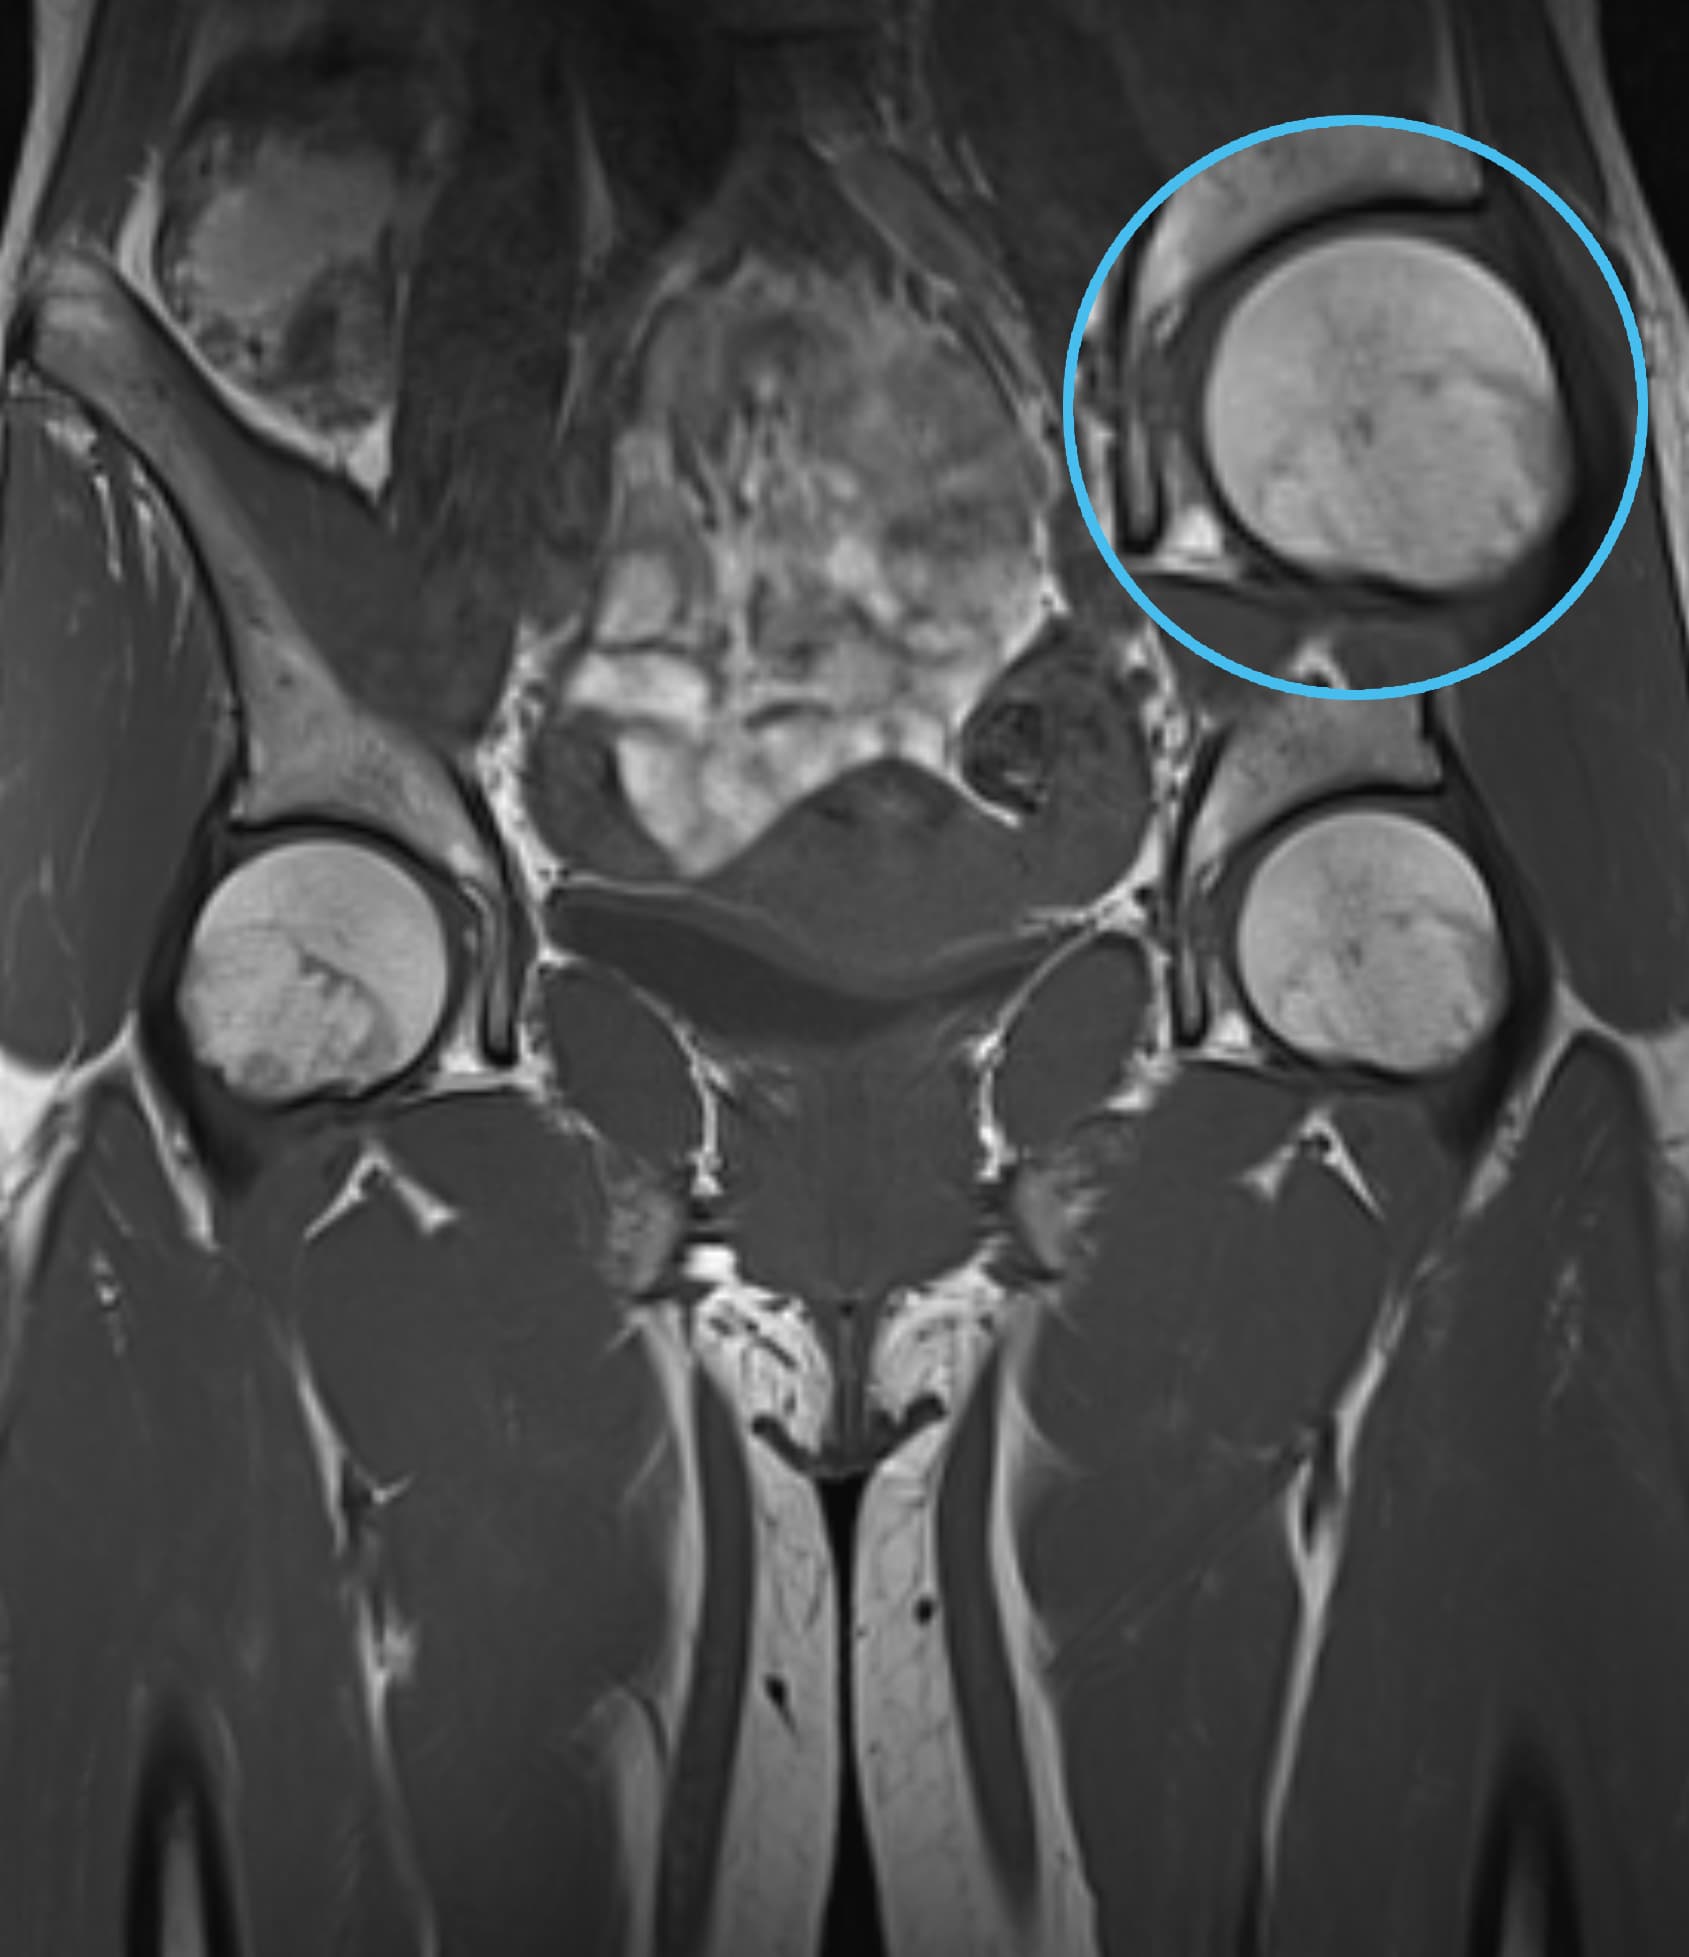

See real-world examples of SwiftMR™ across various MRI systems and anatomical regions

Scan time 04:53

Scan time 1:46